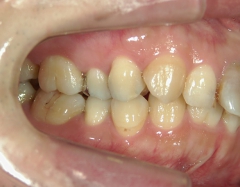

矯正歯科 治療前矯正歯科 治療前

矯正歯科 治療前 上顎の左右4番計2本を抜歯し叢生を改善。

no.24_8228_治療前_右.jpgno.24_8228_治療前_正面.jpgno.24_8228_治療前_左.jpg